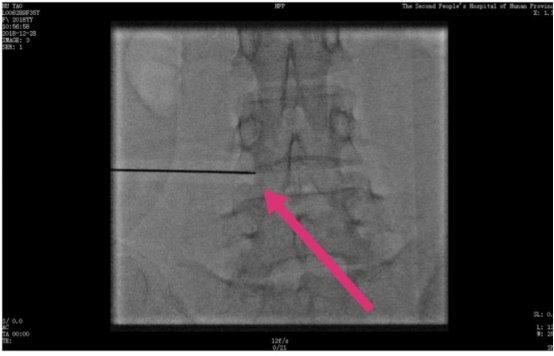

近日,湖南省第二人民醫(yī)院腫瘤科為一例頑固性癌痛患者實施了DSA引導(dǎo)下選擇性神經(jīng)根脈沖射頻術(shù),緩解了患者長達(dá)3年的頑固疼痛。

通過朋友的介紹,她找到了湖南省第二人民醫(yī)院腫瘤科。腫瘤科尹威醫(yī)生在仔細(xì)的分析了她的脊柱磁共振后,表示可以嘗試通過手術(shù)的辦法來治療,緩解患者的疼痛。入院后第三天,醫(yī)生為其實施了DSA引導(dǎo)下選擇性神經(jīng)根脈沖射頻術(shù),術(shù)后,處于清醒狀態(tài)下的王女士在家人的攙扶下走了幾步,頓覺渾身輕松起來。術(shù)后的當(dāng)晚,王女士完全沒有依靠鎮(zhèn)痛藥,便安靜入睡了,用她自己的話說,“這是三年來,最美麗的一個夜晚”!

什么是選擇性神經(jīng)根脈沖射頻術(shù)呢?尹威醫(yī)師解釋,選擇性神經(jīng)根脈沖射頻術(shù)就是一種靶向神經(jīng)麻醉阻滯術(shù),首先借助磁共振和體格檢查把主管軀體疼痛的感覺神經(jīng)找出來,然后將一根裝滿藥物的導(dǎo)管在DSA設(shè)備引導(dǎo)下把導(dǎo)管送達(dá)該感覺神經(jīng)的根部------也就是神經(jīng)起源的地方,實施局部麻醉,讓它感覺不到疼痛,這樣一來,疼痛的問題便迎刃而解了。

像上述這位患者,在術(shù)前就準(zhǔn)確的判斷她的疼痛是一個發(fā)生于腰骶部的神經(jīng)病理性疼痛,于是,醫(yī)生精準(zhǔn)實施靶向麻醉神經(jīng)根部,讓她的疼痛傳導(dǎo)通路受阻,以致于患者在術(shù)后即刻就能達(dá)到很好的止痛效果,解決了困擾患者3年來的難題,而且副反應(yīng)小,術(shù)后康復(fù)快。